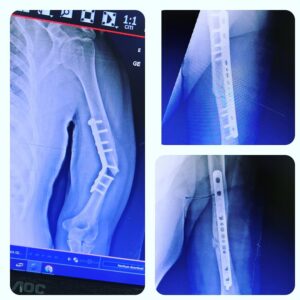

Galeria